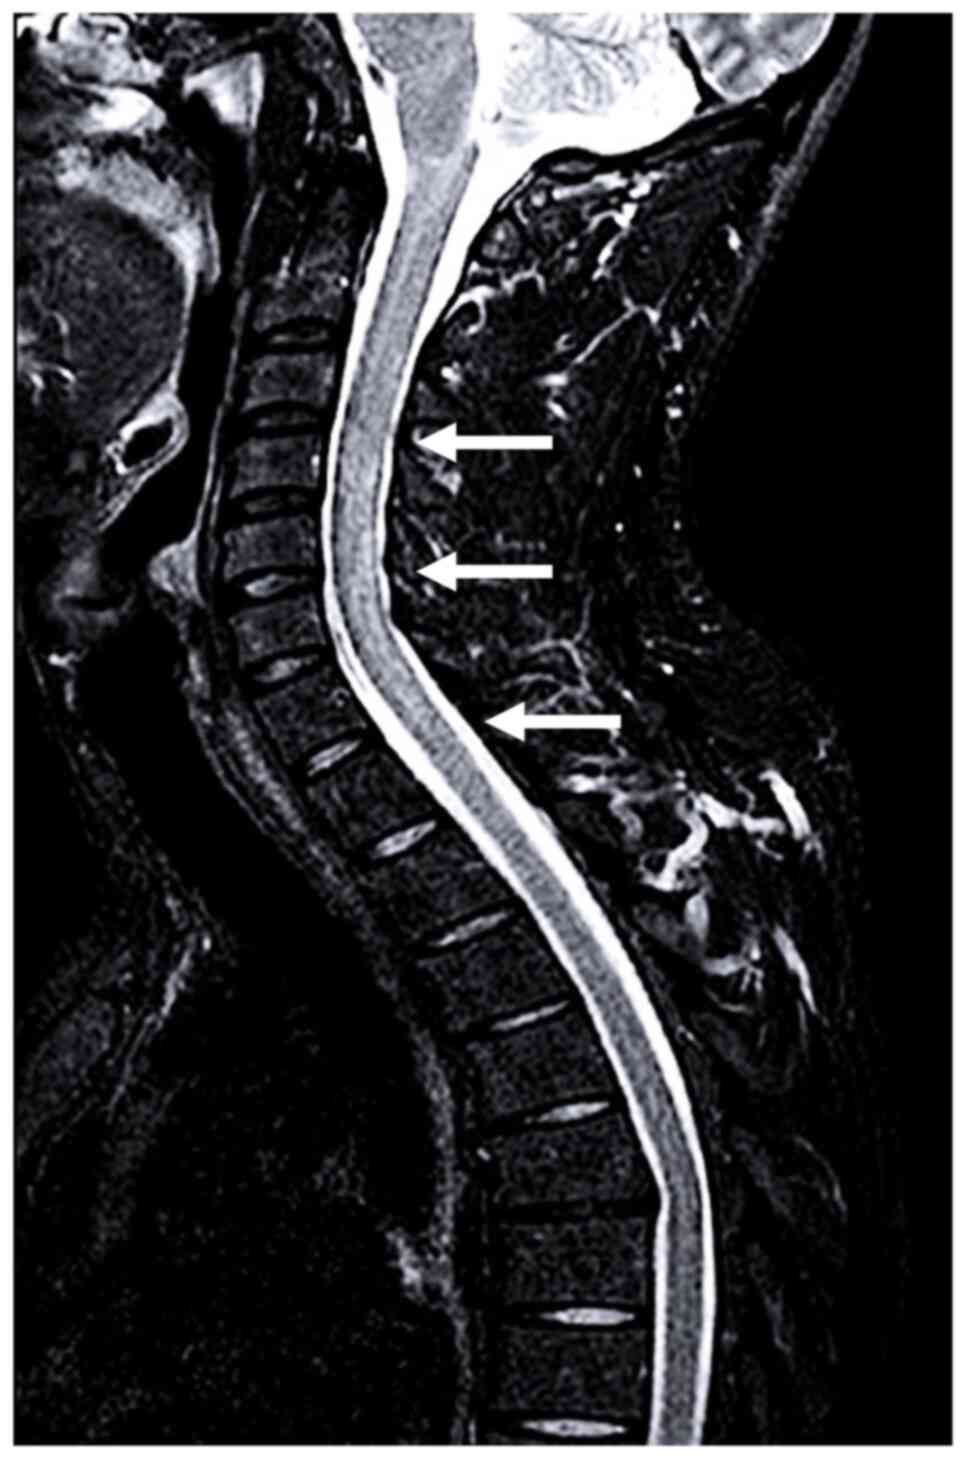

Figure 2

Brain MRI and MR venography findings. MRI (A) axial and (B) coronal sequences showing right parietal fluid-attenuated inversion recovery hyperintensity involving postcentral and precentral gyri (arrowhead). MR venography displaying superior sagittal sinus stenosis (arrows) in (C) axial and (D) coronal views. MR, magnetic resonance; MRI, MR imaging.

A diagnosis of MOGAD was made according to the International MOGAD Panel criteria (1), based on a core clinical demyelinating event (myelitis) with supporting MRI features of LETM, positive MOG-IgG antibodies and seronegative AQP4-IgG, after excluding alternative diagnoses. The patient underwent high-dose intravenous methylprednisolone therapy (1,000 mg per day for 5 days), followed by oral prednisone (50 mg daily). The patient fully recovered and was discharged after 10 days with a prescribed tapering of prednisone over 1 month. However, at 3 days post-discharge, the patient returned to the Emergency Department of ‘Bianchi-Melacrino-Morelli’ Hospital due to a focal to bilateral epileptic seizure, preceded by 2 days of continuous right frontotemporal headaches. Neurological examination revealed mild left hemiparesis and drowsiness, with a National Institutes of Health Stroke Scale (NIHSS) score of 4(7). An urgent brain computed tomography scan showed a right cortical parietal hypodense lesion. Brain MRI revealed a fluid-attenuated inversion recovery-hyperintense right frontoparietal lesion, and an MRI angiogram showed absence of flow in the right superficial cortical veins and superior sagittal sinus, confirming CVT (Fig. 2).